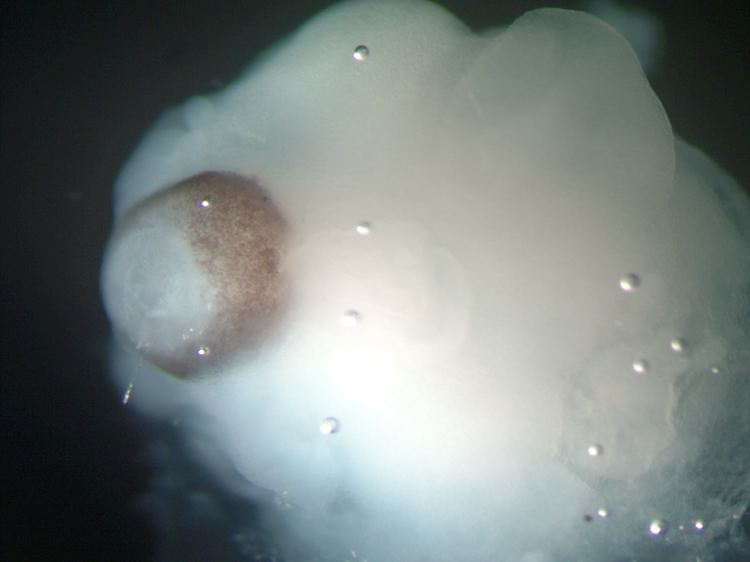

Mikroskopische Aufnahme von Gehirngewebe neben entstehendem Netzhautgewebe (braun eingefärbte Region) bei einem cerebralen Organoid.

(Foto: dpa)